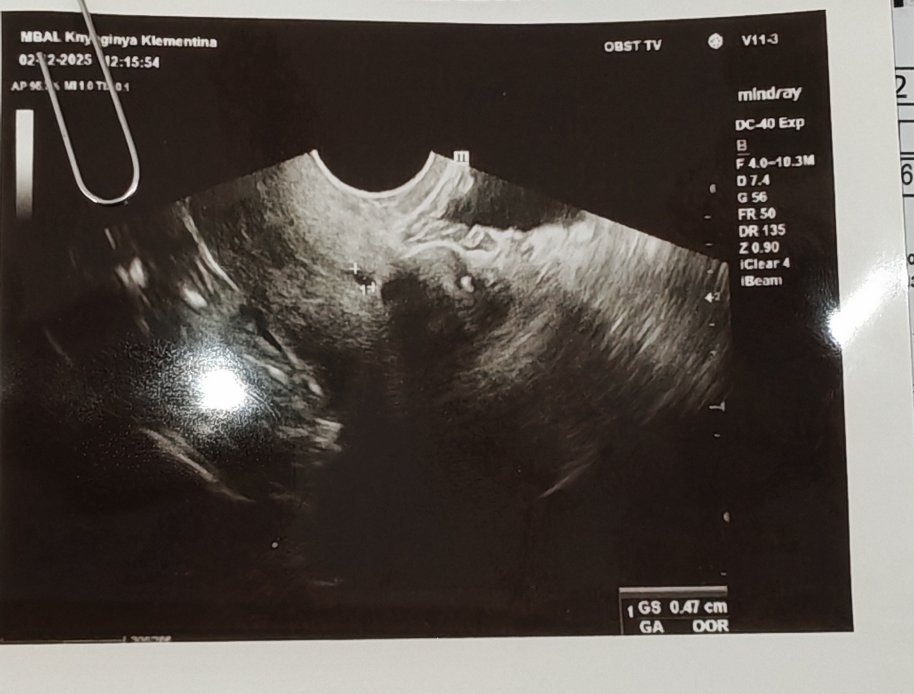

Здтавейте, моля з помощ! Случвало ли се е на някоя да не се види плоден са в 6 седмица, нито в матката, нито извън нея? Пуснах бета- чхг на 02.12 беше 155,на 04.12 беше 1040 и на 08.12 беше 2217.

Бях на друг лекар пак не видя, а чхг днес е 3484.. Моята лекарка мисли, чв е извънматочна, но аз не мисля така. Няма нито в матката, нито извън нея а чхг е нормално според мен

В 6-та седмица вече се виждат плоден сак и ембрион, а с хубава апаратура се чува и пулс. Може просто апаратът да не е достатъчно точен или да има някакъв проблем. Добре е да потърсите второ мнение.